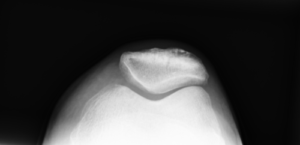

膝関節伸展の主力で、膝蓋骨を外上方へ牽引する線維配列を持つ(外側膝蓋支帯と連結)。

ITBや外側膝蓋支帯の柔軟性低下は膝蓋大腿関節痛(PFPS)や外側偏位の誘因となる。